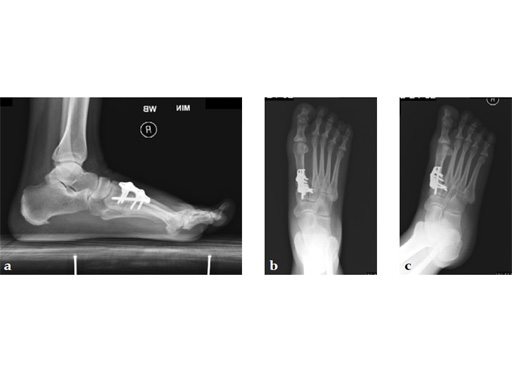

A 60-year-old woman with pes plano abductovalgus (flatfoot deformity).

Case provided by Andrew Sands, New York, New York, USA

The patient was treated by headless compression screw 6.5 tuber osteotomy, TMT plantarflexing osteotomy, and first TMT fusion a plate.